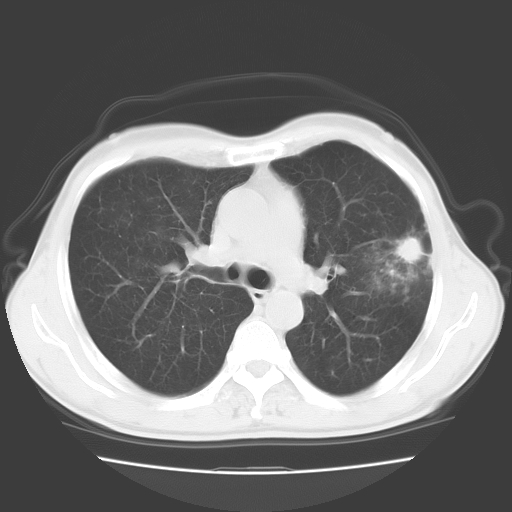

以下是引用随光逐影在2008-11-20 23:02:00的发言:[br]1)考虑左肺上叶周围型肺癌可能性大。2)两肺散在性肺泡积血。[br][br][本贴已被 随光逐影 于 2008-11-20 23:09:31 修改过]

以下是引用drzhang8888在2008-11-20 22:20:00的发言:[br]密集的短毛刺,血管集束,胸膜凹陷,周边型肺癌可能性大,另双肺多发磨玻璃影,考虑感染

以下是引用流浪星在2008-11-20 22:28:00的发言:[br]左肺上叶近外围区见一类圆形结节影,毛刺征、胸膜尾征阳性,临近肺组织见多发渗出灶。考虑1,炎症性病变。 2.周围性肺癌。建议抗炎治疗后复查。

以下是引用qc80012345在2008-11-21 5:53:00的发言:[br]支持;周围型肺癌诊断。增强扫描。